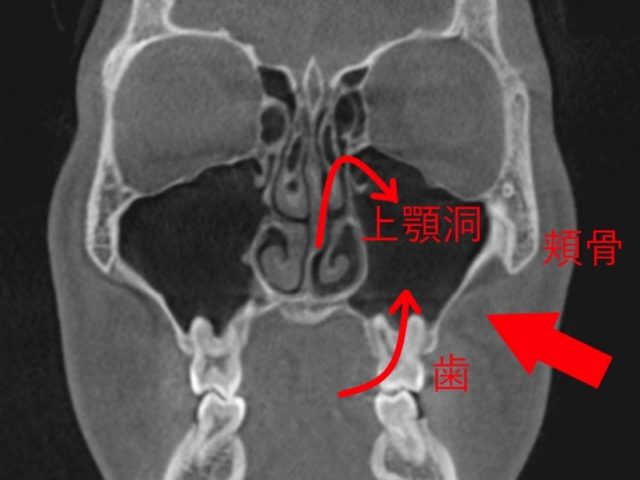

歯性上顎洞炎に なりやすい人 なりにくい人

歯性上顎洞炎になりやすい人

歯根と、上顎洞が近い人です。

上は、上顎洞内に、

大臼歯の歯根が

飛び出しています。

もし、この根が化膿すると、

上顎洞に炎症が波及しやすいでしょう。

この様な方は、

歯性上顎洞炎になりやすいと思われます。

歯性上顎洞炎の予防

上の奥歯は、上顎洞に近い

上図の様に、

上顎大臼歯の根は、

上顎洞の中に飛び出している

事が良くあります。

特に、

上顎大臼歯、

上6番、7番の歯です。